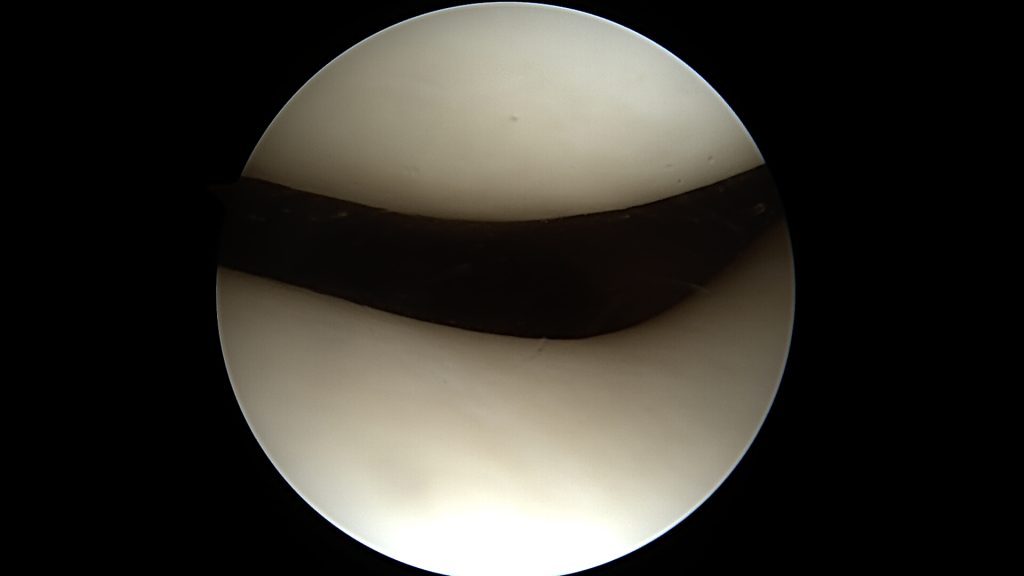

Chrząstka stawowa pokrywa powierzchnie ślizgowe w łożysku jakim jest staw. Jest to biała, lśniąca tkanka o trójwymiarowej budowie odpornej na zgniatanie oraz ścieranie. W kolanie jej grubość wynosi od 2 do 4 mm (najgrubsza warstwa znajduje się na rzepce).

Do uszkodzenia chrząstki stawowej dochodzi w momencie urazu kolana, powtarzających się obciążeń czy chorób jak np. reumatoidalne zapalenie stawów. Może też być ona uszkadzana wtórnie poprzez inne elementy stawu (np.: uszkodzona łąkotka, ciało wolne). Wyróżniamy cztery stopnie jej uszkodzenia: